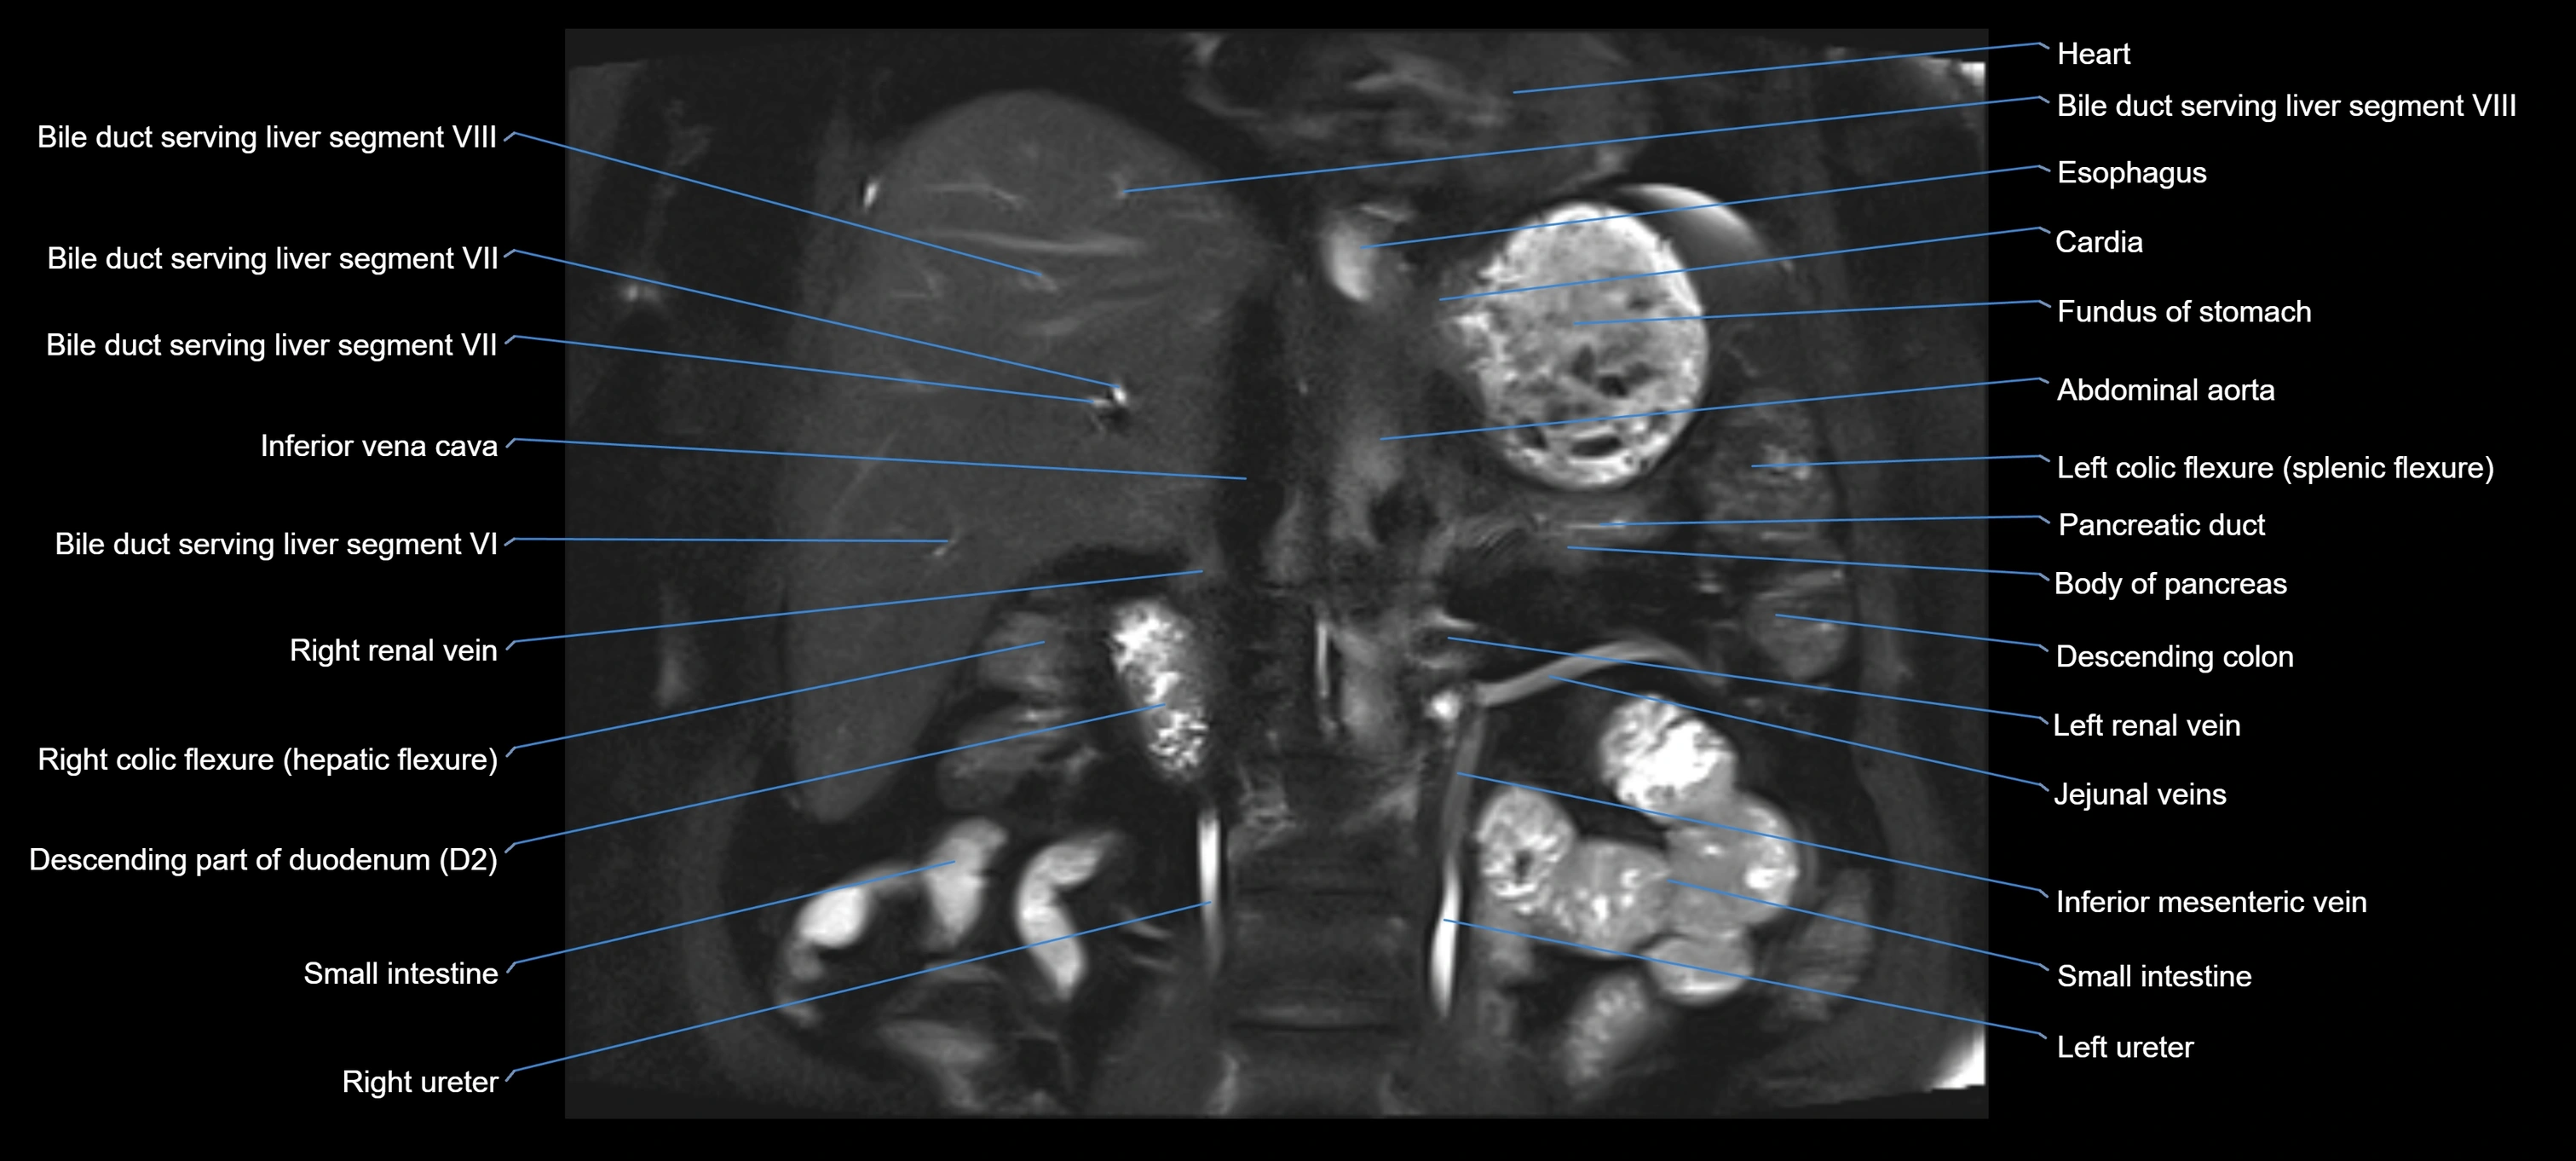

MRI image

image